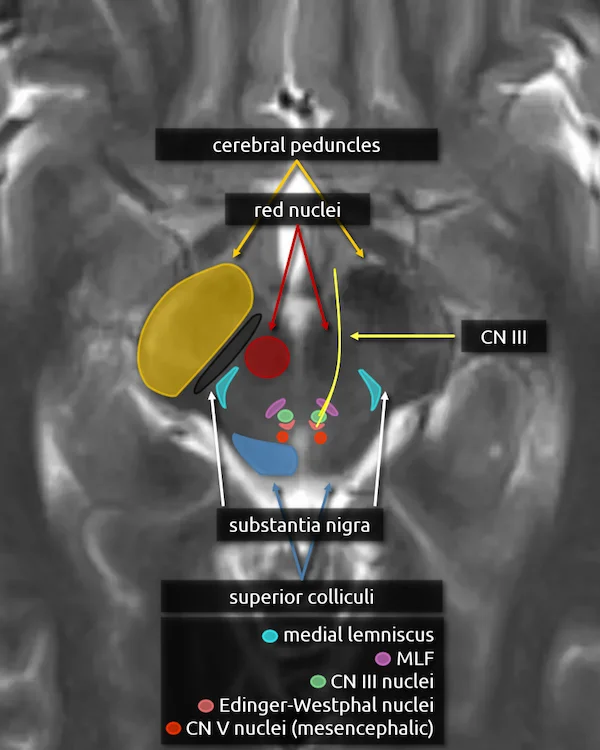

1. Cerebral peduncles

2. Superior colliculi

3. Red nucleus

4. Substantia nigra

5. Medial lemniscus

6. Medial longitudinal fasciculus (MLF)

7. Oculomotor nucleus (CN III)

The oculomotor nucleus is located in the upper midbrain posterior to the red nuclei anterior to the cerebral aqueduct. It is one of two nuclei that contributes to the oculomotor nerve. It provides efferent somatic motor fibers.

Lesions involving the oculomotor nucleus are rare but may cause a specific syndrome with bilateral deficits from a unilateral lesion. A single subnucleus spans the midline and supplies the bilateral levator palpebrae muscles, responsible for elevating the eyelids. Additionally, the subnucleus that supplies the superior rectus crosses the midline and supplies both muscles. As a result, nuclear CN III palsy may present with bilateral ptosis and weakness of the bilateral superior rectus muscles. A lesion of solely the nerve fascicle should not cause these symptoms.

8. Edinger-Westphal nucleus

The Edinger-Westphal nucleus is located immediately posterior to the oculomotor nucleus and is the second nucleus that contributes to the oculomotor nerve. It provides parasympathetic motor fibers.

9. Oculomotor nerve (CN III)

The oculomotor nerve exits the brainstem medially after coursing through portions of the red nucleus and substantia nigra. The nerve courses slightly inferior to the axial diagrammatic depiction below, traveling just underneath the mamillary bodies.

Somatic motor innervation:

a. Extraocular muscles (besides the superior oblique and lateral rectus)

b. Levator palpebrae superioris (responsible for elevation of the eyelid)

Parasympathetic motor innervation:

a. Sphincter pupillae muscle (responsible for pupillary constriction)

b. Ciliary body (responsible for light accommodation)

CN III palsy causes the ipsilateral eye to rest in a "down-and-out" position due to unopposed action of the lateral rectus and superior oblique muscles, which are innervated by CN VI and CN IV, respectively. There may also be a unilateral ptosis. The CN III parasympathetic fibers are located on the periphery of the nerve. Because of this, CN III palsy due to compression, e.g., by an aneurysm or a mass, causes a dilated nonreactive pupil. Pupil-sparing CN III palsy is more likely to be due to a medical cause, such as diabetic or hypertensive microangiopathy.

10. Mesencephalic nucleus of the trigeminal nerve (CN V)

The mesencephalic nucleus courses through the midbrain to the mid pons and is involved in proprioception of the structures surrounding the mouth, e.g., the muscles of mastication, temporomandibular joint, teeth, and hard palate.

A not so clinically important factoid that makes this nucleus unique is that axons from this nucleus go directly to target tissues, while other brainstem nuclei first have synapses onto primary sensory neurons in ganglia outside the brainstem (e.g. the trigeminal ganglion, see "trigeminal nerve in sagittal" in level 3). Some fibers from the mesencephalic nucleus also go to the motor nucleus of the trigeminal nerve to mediate bite control and the jaw-jerk reflex.